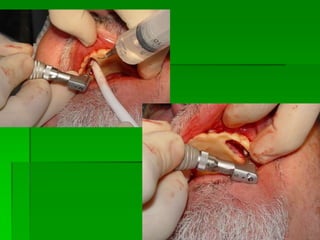

PRIMEIRA FASE CIRÚRGICAMOTOR PARA CIRURGIAPRIMEIRA FASE CIRÚRGICAKITS CIRÚRGICOSTipos de implante e indicações

Irrigação

Seqüência de Brocas